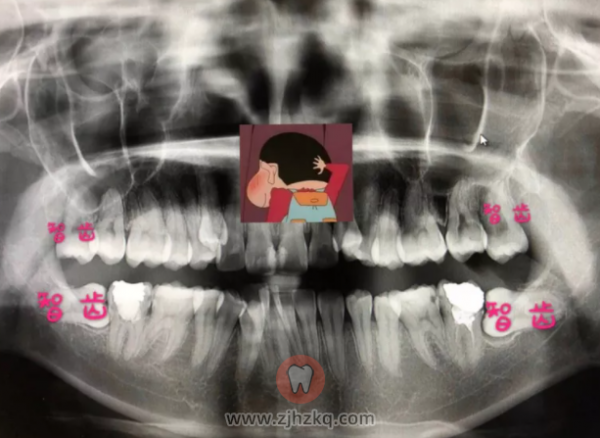

◆拔牙:检查有四颗智齿,其中下面两个还是横长的,看图片也可以看出来,所以动了两个小手术拔了,上面左四右四下面左五右三,共拔了八颗牙!听医生建议拔牙的颗数,因为她们是专业的。